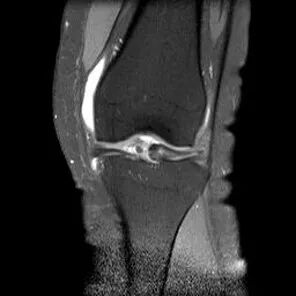

半月板水平撕裂

1、水平撕裂

2、较少见3、III级高信号与胫骨平台平行,到达半月板的游离缘或一侧关节面

(半月板水平撕裂)